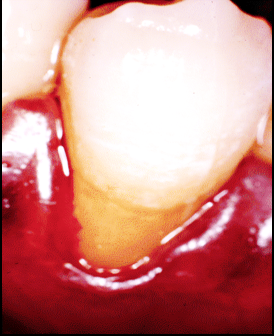

Fenestration

“Window” where exposed root is covered only by periosteum and gingiva, not bone

Dehiscence

Root exposure as V or U shape

From cervical region that extends inferiorly

Anterior teeth, premolars, and mesiobuccal roots of first molars